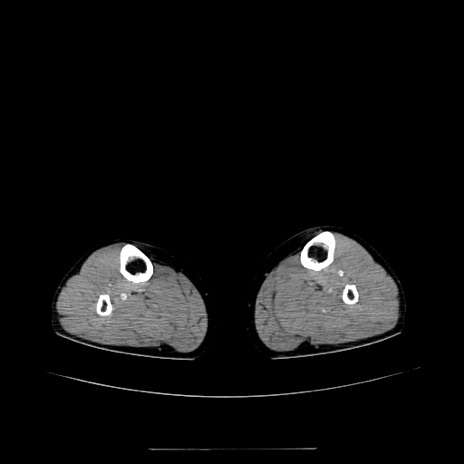

症例5(横断像)

【症例】70歳代女性

【主訴】お腹が張る

【現病歴】1週間くらい前から腹部膨満の自覚あり。昨日夜から増悪したため、本日救急外来受診。

【身体所見】意識清明、BT 36.5℃、BP 165/106mmHg、HR 80bpm、SpO2 98%、腹部:膨満、軟、自発痛・圧痛なし、触診にて不快感あり、腸蠕動音:減弱

【データ】WBC 12600、CRP 1.04